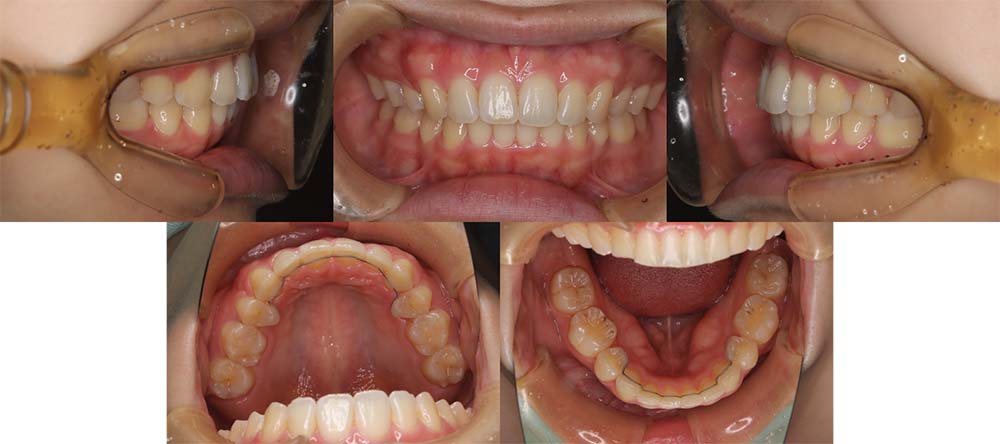

| 症例分類 | 上顎前突、叢生 |

| 診断名 | 上下叢生を伴う骨格性および歯性上顎前突 |

| 主訴 | 歯並びが悪いのが気になる、口元が気になる |

| 年齢 | 19歳5ヶ月 |

| 性別 | 女性 |

| 抜歯部位 | 上の左右第一小臼歯(2本) |

| 使用装置 | 上下裏側のワイヤー装置 |

| 治療期間 | 2年5ヶ月 |

| 保定装置 | 固定式保定装置、取り外し式保定装置(8時間) |

| 費用 |

[検査・診断料] ¥49,500 [基本施術料] ¥1,331,000 [調整料] ¥5,500/回 [抜歯] ¥5,500/本 [保定装置] ¥55,000(税込) 抜歯や虫歯治療は他院にて費用が別途かかります。(抜歯¥4,000〜10,000/本)

上顎前突で上の歯がかなり前にきているため、上顎両側第一小臼歯を抜去して治療を行いました。上の前歯をしっかりと舌側に移動しないといけないため、矯正用アンカースクリューを使用しました。また、下顎はわずかに歯の間の削合(ディスキング)を行い、初診時より歯が前方に出ないように治療を進めました。

口唇閉鎖不全もありましたが、上の前歯が舌側に移動することにより改善することができ、問題なく咬合させることができました。